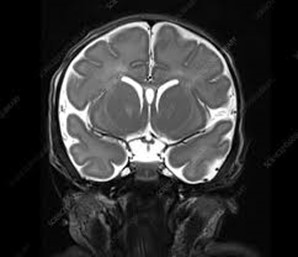

Magnetic resonance imaging (MRI) is a medical imaging technique used in radiology to form pictures of the anatomy and the physiological processes of the body. MRI scanners use strong magnetic fields, magnetic field gradients, and radio waves to generate images of the organs in the body

MRI scan of the body is mostly performed to evaluate:

• organs of the chest and abdomen—including the heart, liver, biliary tract, kidneys, spleen, bowel, pancreas, and adrenal glands.